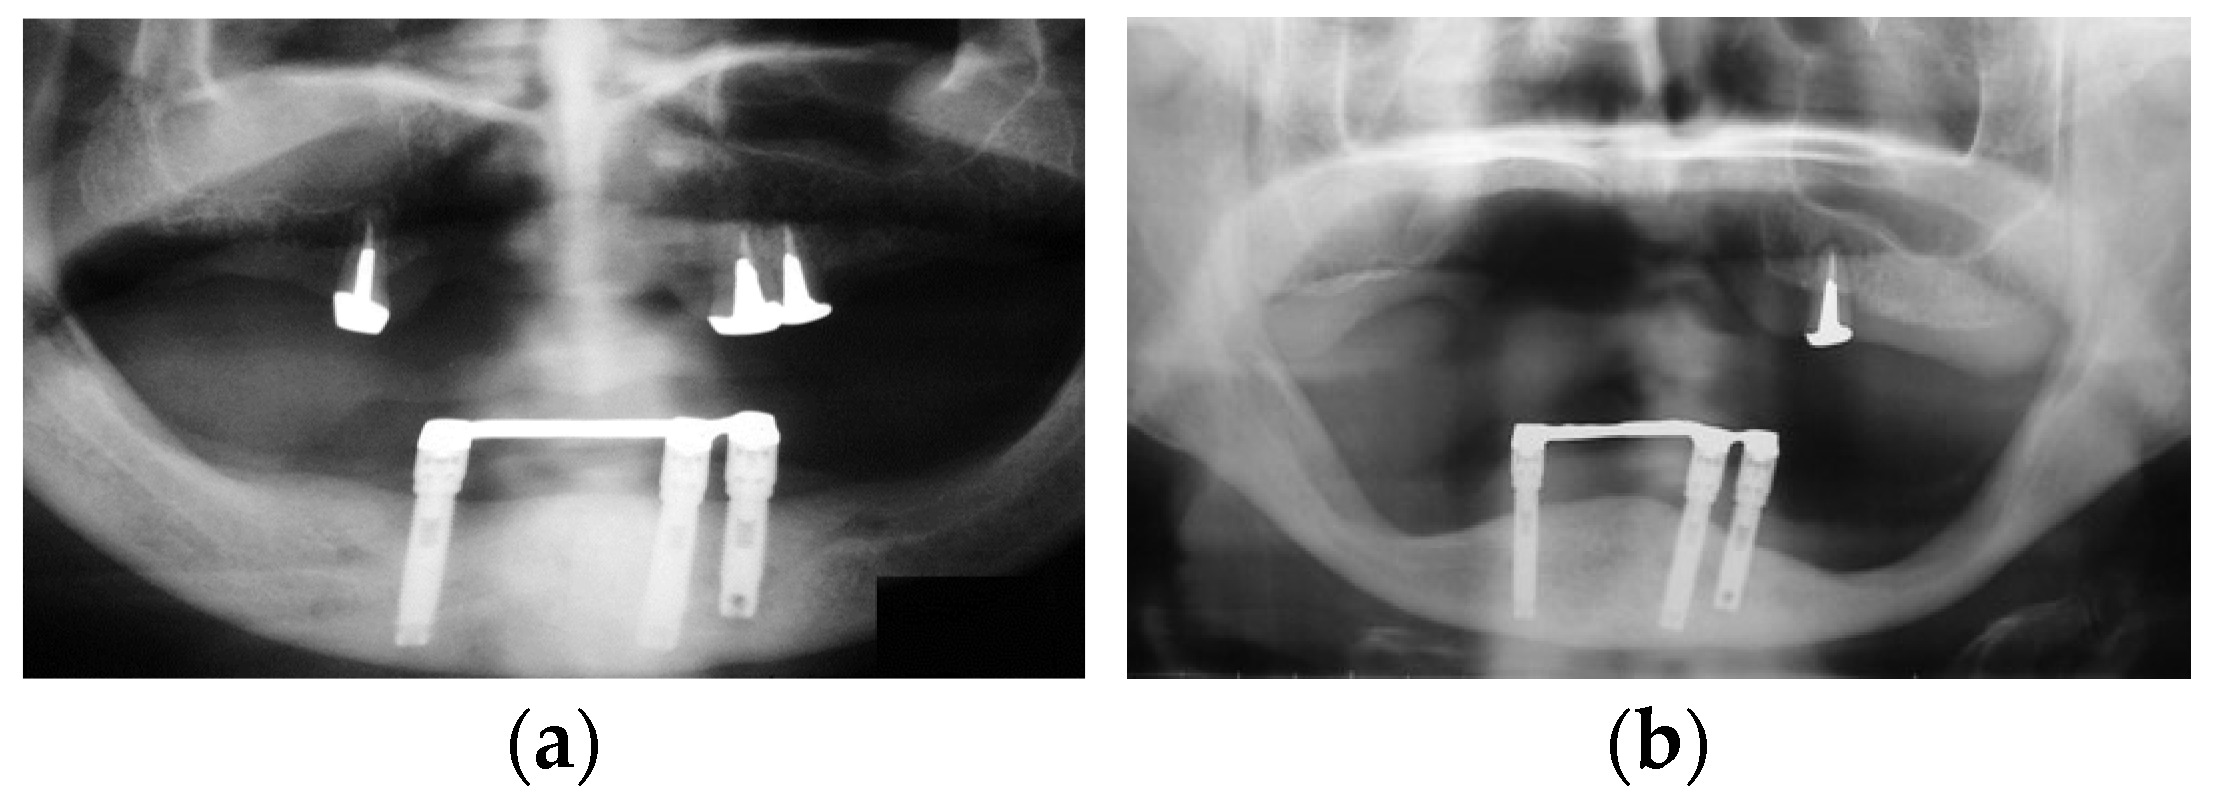

However, there have been multiple reports that have presented mandibular implant-supported overdenture-induced anterior hyperfunction, subsequent bone resorption, and the formation of flabby hyperplastic tissues at the anterior site beneath maxillary complete denture base-opposing implants [38,39,40,41,42,43]. These reports suggested the risk of mandibular implant-supported overdentures for destructive changes on the maxillary anterior site. In fact, we experienced the negative effects of mandibular implant-supported overdentures on maxillary anterior sites and mandibular posterior sites (Figure 8). In addition, we also experienced a clinical case where a mandibular implant-supported fixed prosthesis in a patient with only maxillary anterior teeth worked as anterior hyperfunction and root fracture of the maxillary anterior tooth was confirmed. This patient’s case resulted in edentulous maxilla due to sequential root fracture and the patient was rehabilitated with maxillary complete denture, unfortunately (Figure 9). These findings suggest the risk of mandibular implant-supported prostheses working as anterior hyperfunction. Meanwhile, contrary to these reports, a recent systematic review and meta-analysis revealed that no significant difference was detected in maxillary anterior bone resorption between patients with mandibular two-implant-supported overdentures and with conventional mandibular complete dentures [18]. The retention mechanism (attachment types of overdentures), the relining of the maxillary complete denture, occlusal condition, and stages of edentulism might be associated with bone resorption, and the necessity of a well-designed randomized clinical study was suggested. However, it is important to note that mandibular implant-supported overdentures or mandibular implant-supported fixed prostheses as alternatives for conventional removable prostheses may make the problems complicated depending on the interventions.

Figure 8. Bone resorption in a patient with implant-supported overdenture: (a) a panoramic X-ray image at the delivery of overdenture; (b) a panoramic X-ray image at 19-year follow-up. Source: the authors.